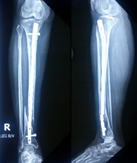

Case-I

19 years, male;

Broken ILIMN of femur (Ipsilateral fracture shaft of femur with tibia and fibula, H/O-poly-trauma) (Figure 1-4). Infection and non-union are the morbid complications of fracture management. Infections are more common in open fracture also caused by superficial surgical site infection. The incidence of infection in closed long bones fracture 1-2% and it is higher in open fracture, 5% Gustilo type-Ⅰ, 10% Gustilo type-Ⅱ and 15% Gustilo type-Ⅲ8 and surgical site infection (SSI) is 3.6 to 4.8%.9 The fracture complexity and soft tissue damage are the critical factors, influence the risk of infection.

Figure 1 X-ray broken IM nail after fall.

Figure 2&3 Post-operative x-ray after Ilizarov operation.

Figure 4 X-ray after union.